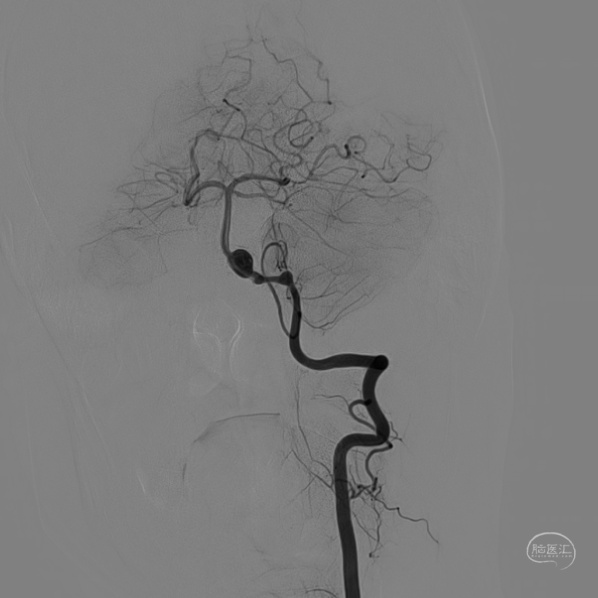

DSA:

术后造影显示动脉瘤内造影剂滞留明显,载瘤动脉通畅。